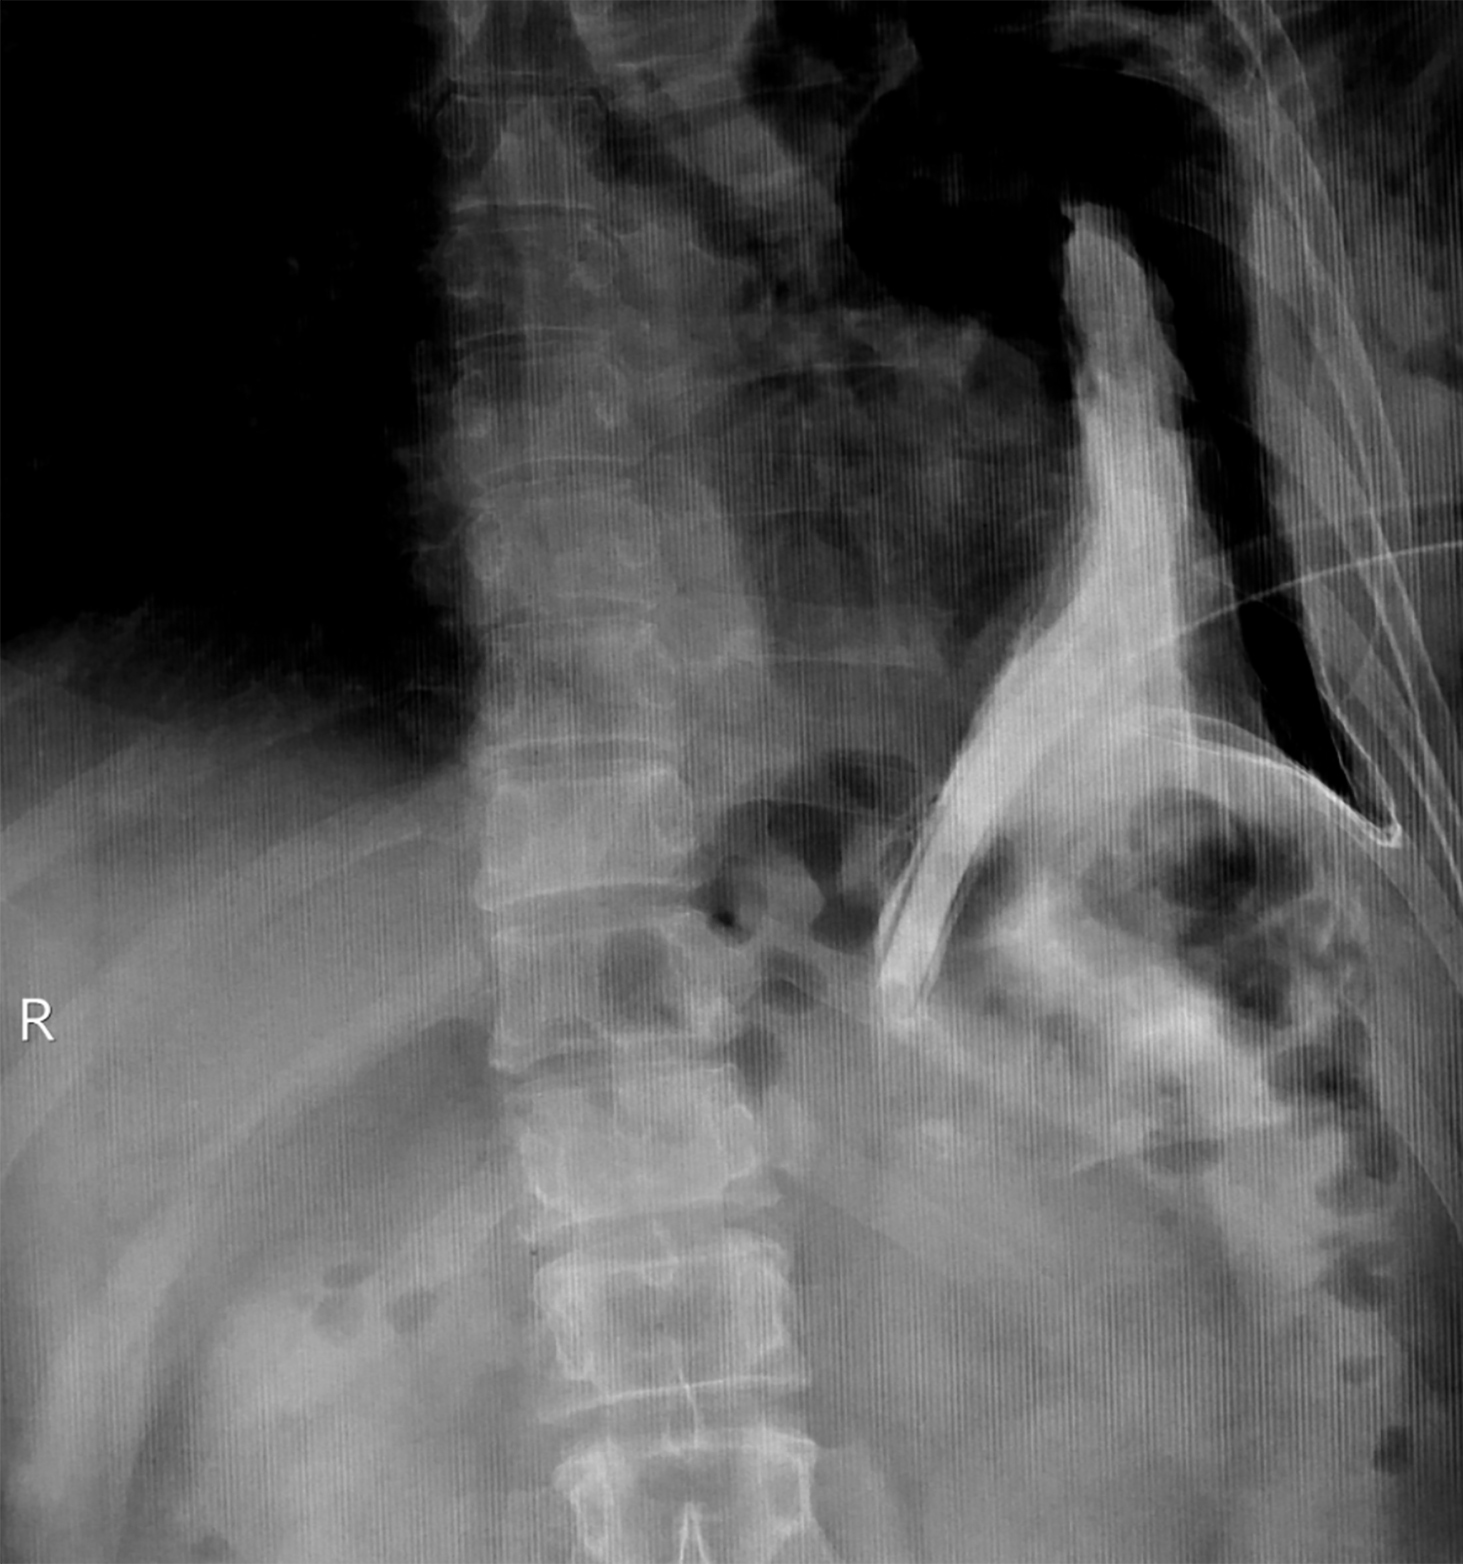

The defect was repaired surgically via laparotomy. Primary repair of rupture of gastric fundus and diaphragm was performed along with establishment of feeding jejunostomy and continued pleural drainage. Postoperative trajectory was smooth. Postoperative barium swallow was performed, which revealed resolution of fistulous communication and normal opacification of the stomach (Figure 3). Patient was discharged 10 days later. He was recovered completely with no sequelae.

Figure 3: Postoperative barium swallow showed complete resolution of fistulous communication and normal opacification of the stomach.